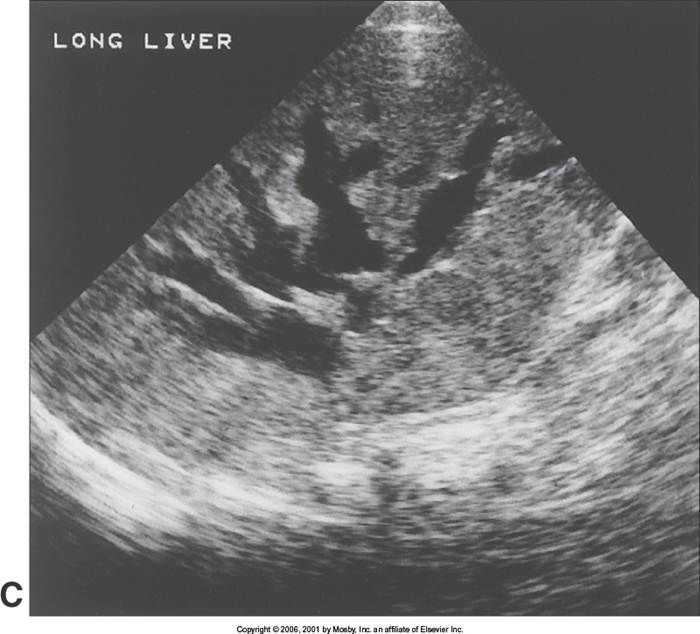

Biliary Obstruction

aka: Double channel

Shot gun

Double barrel

Parallel channel

(dilated biliary duts: A CBD more than 6mm in diameter is considered borderline and more than 10 mm is dilated – will vary by protocol)